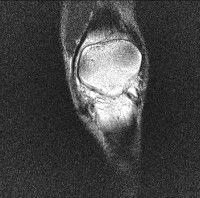

무릎 mri 간단히 봐주실 수 있으시나요 ㅠㅠ

안녕하세요 8년전 십자인대 수술하고 최근 무리한 운동에 무릎 불편감이 생겨서

mri 찍었습니다.

진단결과는 첫 찍은 병원에서 활액막염 이라는 진단을 받았습니다. 혹시 봐주실 수 있으실까요?

올라온 MRI가 단편적이라서 정확한 진단에 어려움이 있지만 십자인대에는 큰 이상이 있지는 않은것 같으며, 무릎관절내 물이 있는 것으로 보아 활액막염의 진단이 맞을 것 같습니다.

하지만 단편적인 영상이기 때문에 촬영병원에서 정확한 판독지 등을 받으시는 것이 좋겠습니다.